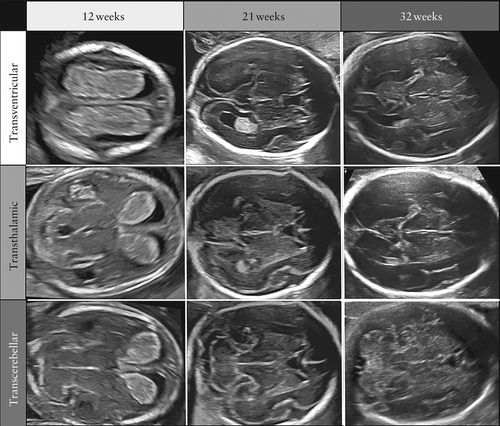

在低风险妊娠的中期扫描中,胎儿CNS筛查检查应包括使用经腹部超声对胎儿的头部和脊柱进行评估。对两个横断平面的评估可以显示相关的大脑结构,从而评估胎儿大脑的解剖完整性。这些平面通常称为侧脑室平面(图2a)和小脑平面(图2b)第三个平面,即所谓的经丘脑平面(图2c),主要用于生物测定。常规检查中应注意的结构包括侧脑室、小脑和延髓池、透明隔腔等结构(CSP)。头部的形状和大脑回声也应在在这些切面上注意(表1)。

图2在三个横断平面上进行胎儿中枢神经系统筛查检查(正常的21周胎儿)。(a)脑室平面,显示侧脑室的前部和后部。逗号形的前角在中线被透明隔分隔(CSP)隔开。图像的远场的侧脑室室后角以及脉络丛(CP),作为测量侧脑室宽度和顶枕裂的解剖参考标志(图像)。(b)在经小脑平面,探头向后倾斜,以描绘中后颅窝的结构:丘脑(Th),小脑半球和小脑蚓部,显示为蝴蝶形,小脑后无回声区,对应枕大池(小脑延髓池)(CM)。(c)经丘脑平面通常用于胎儿头部的生物测量(双顶径,枕额距离和头部周长),低于并平行于脑室平面。在该平面上,还观察到了大脑镰、侧脑室前角和CSP,以及双侧丘脑(Th)和海马回。